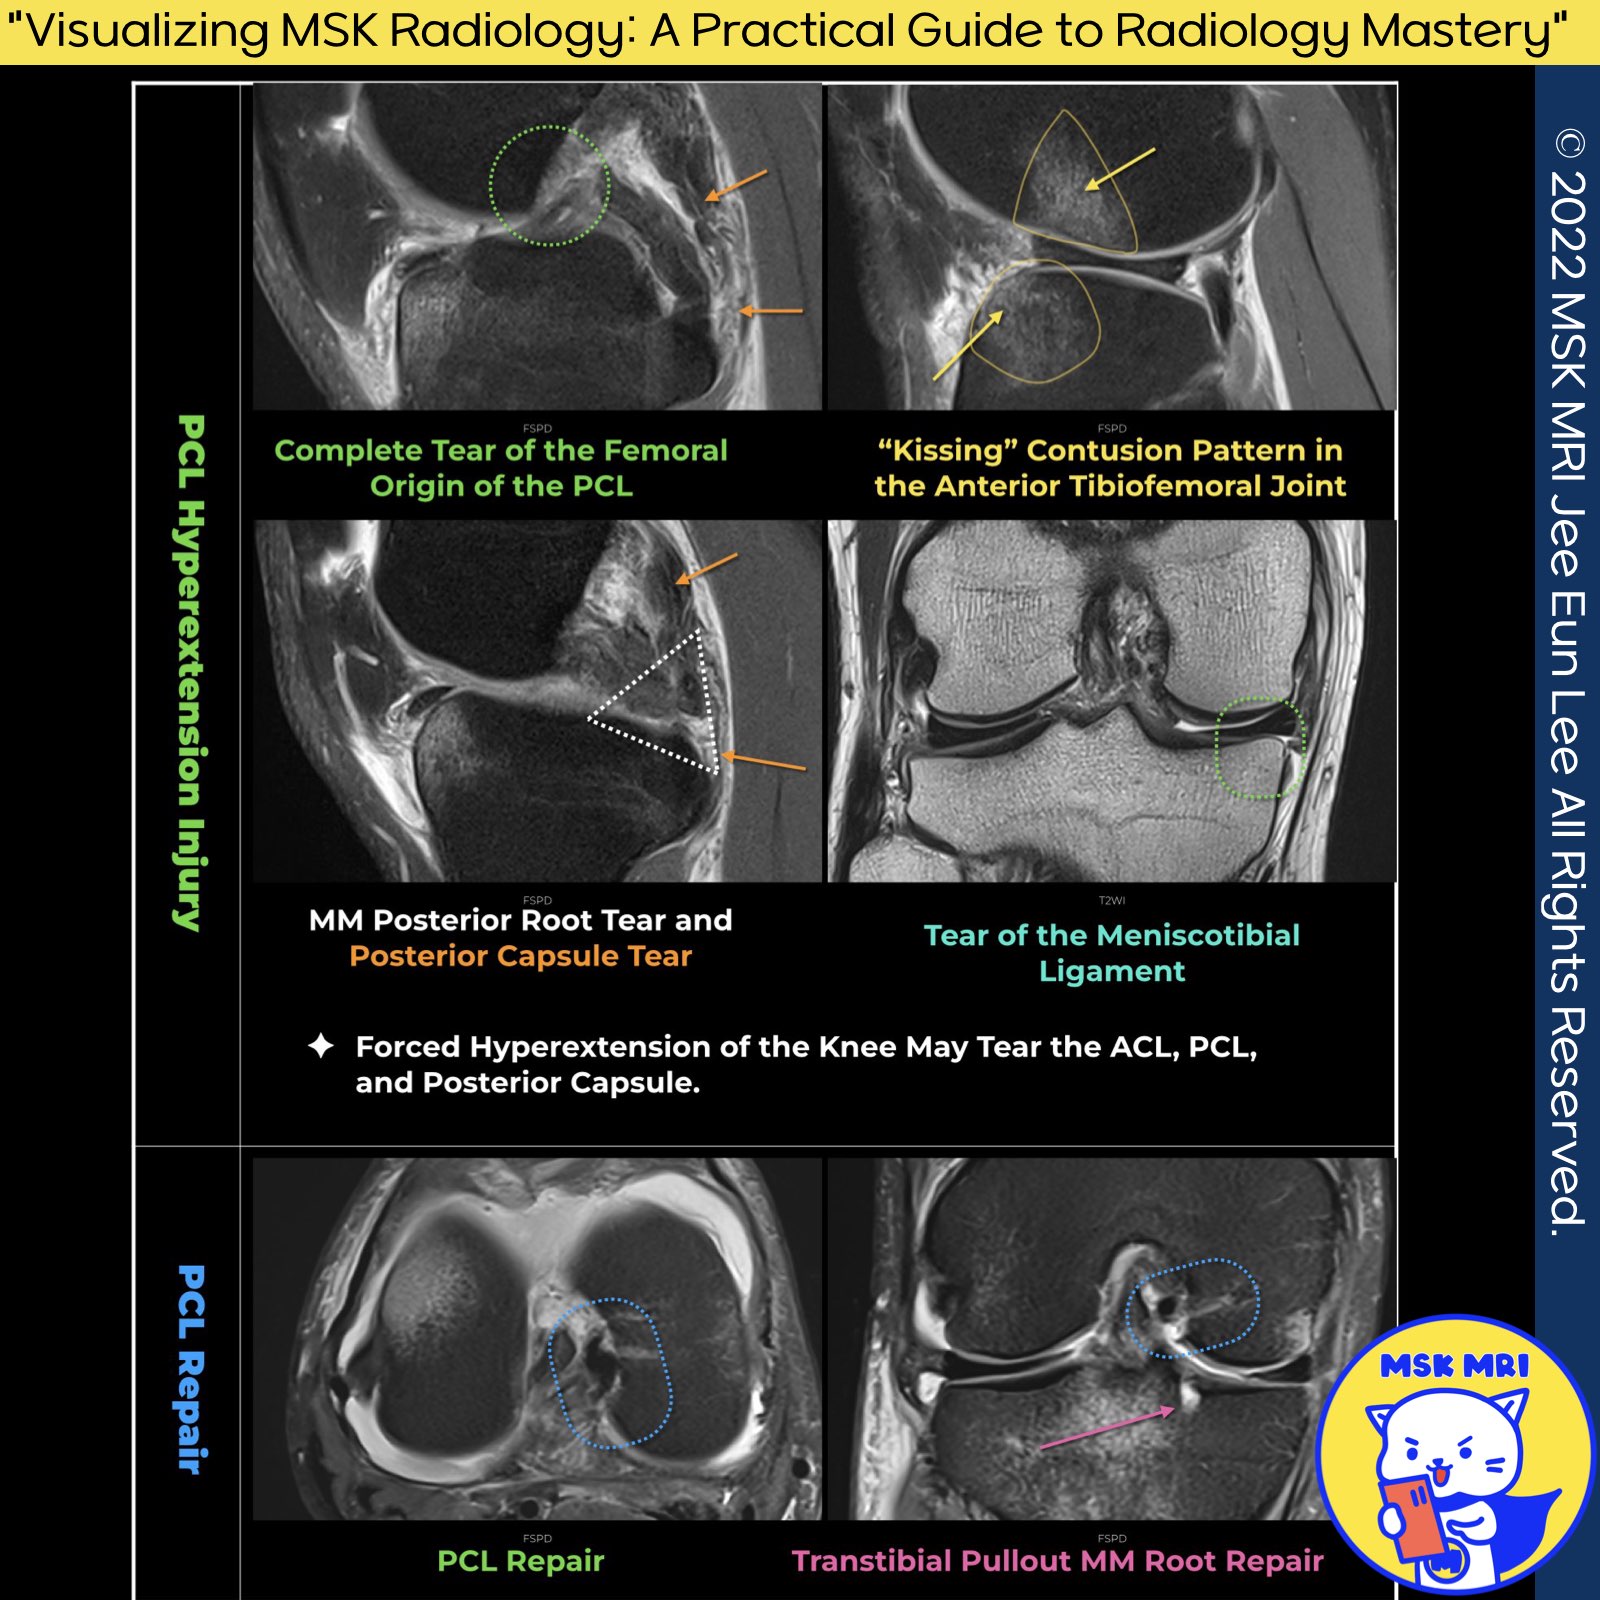

📌 PCL Hyperextension Injury📌

1️⃣Hyperextension Injuries:

- These injuries can lead to contusions of the anterotibial articular surface and the anterior aspect of the femoral condyle.

- Severe hyperextension injuries may also be associated with a tear of the ACL, PCL, posterior capsule, and injuries to the posterolateral or posteromedial corners.

♦️ Rupture of the Meniscotibial Ligament:

- A rupture of the meniscotibial ligament can lead to instability of the meniscus, as this ligament normally keeps the meniscus tightly adhered to the tibia and likely prevents its extrusion.

- When ruptured, the meniscotibial component is associated with pathological mobility of the medial meniscus.